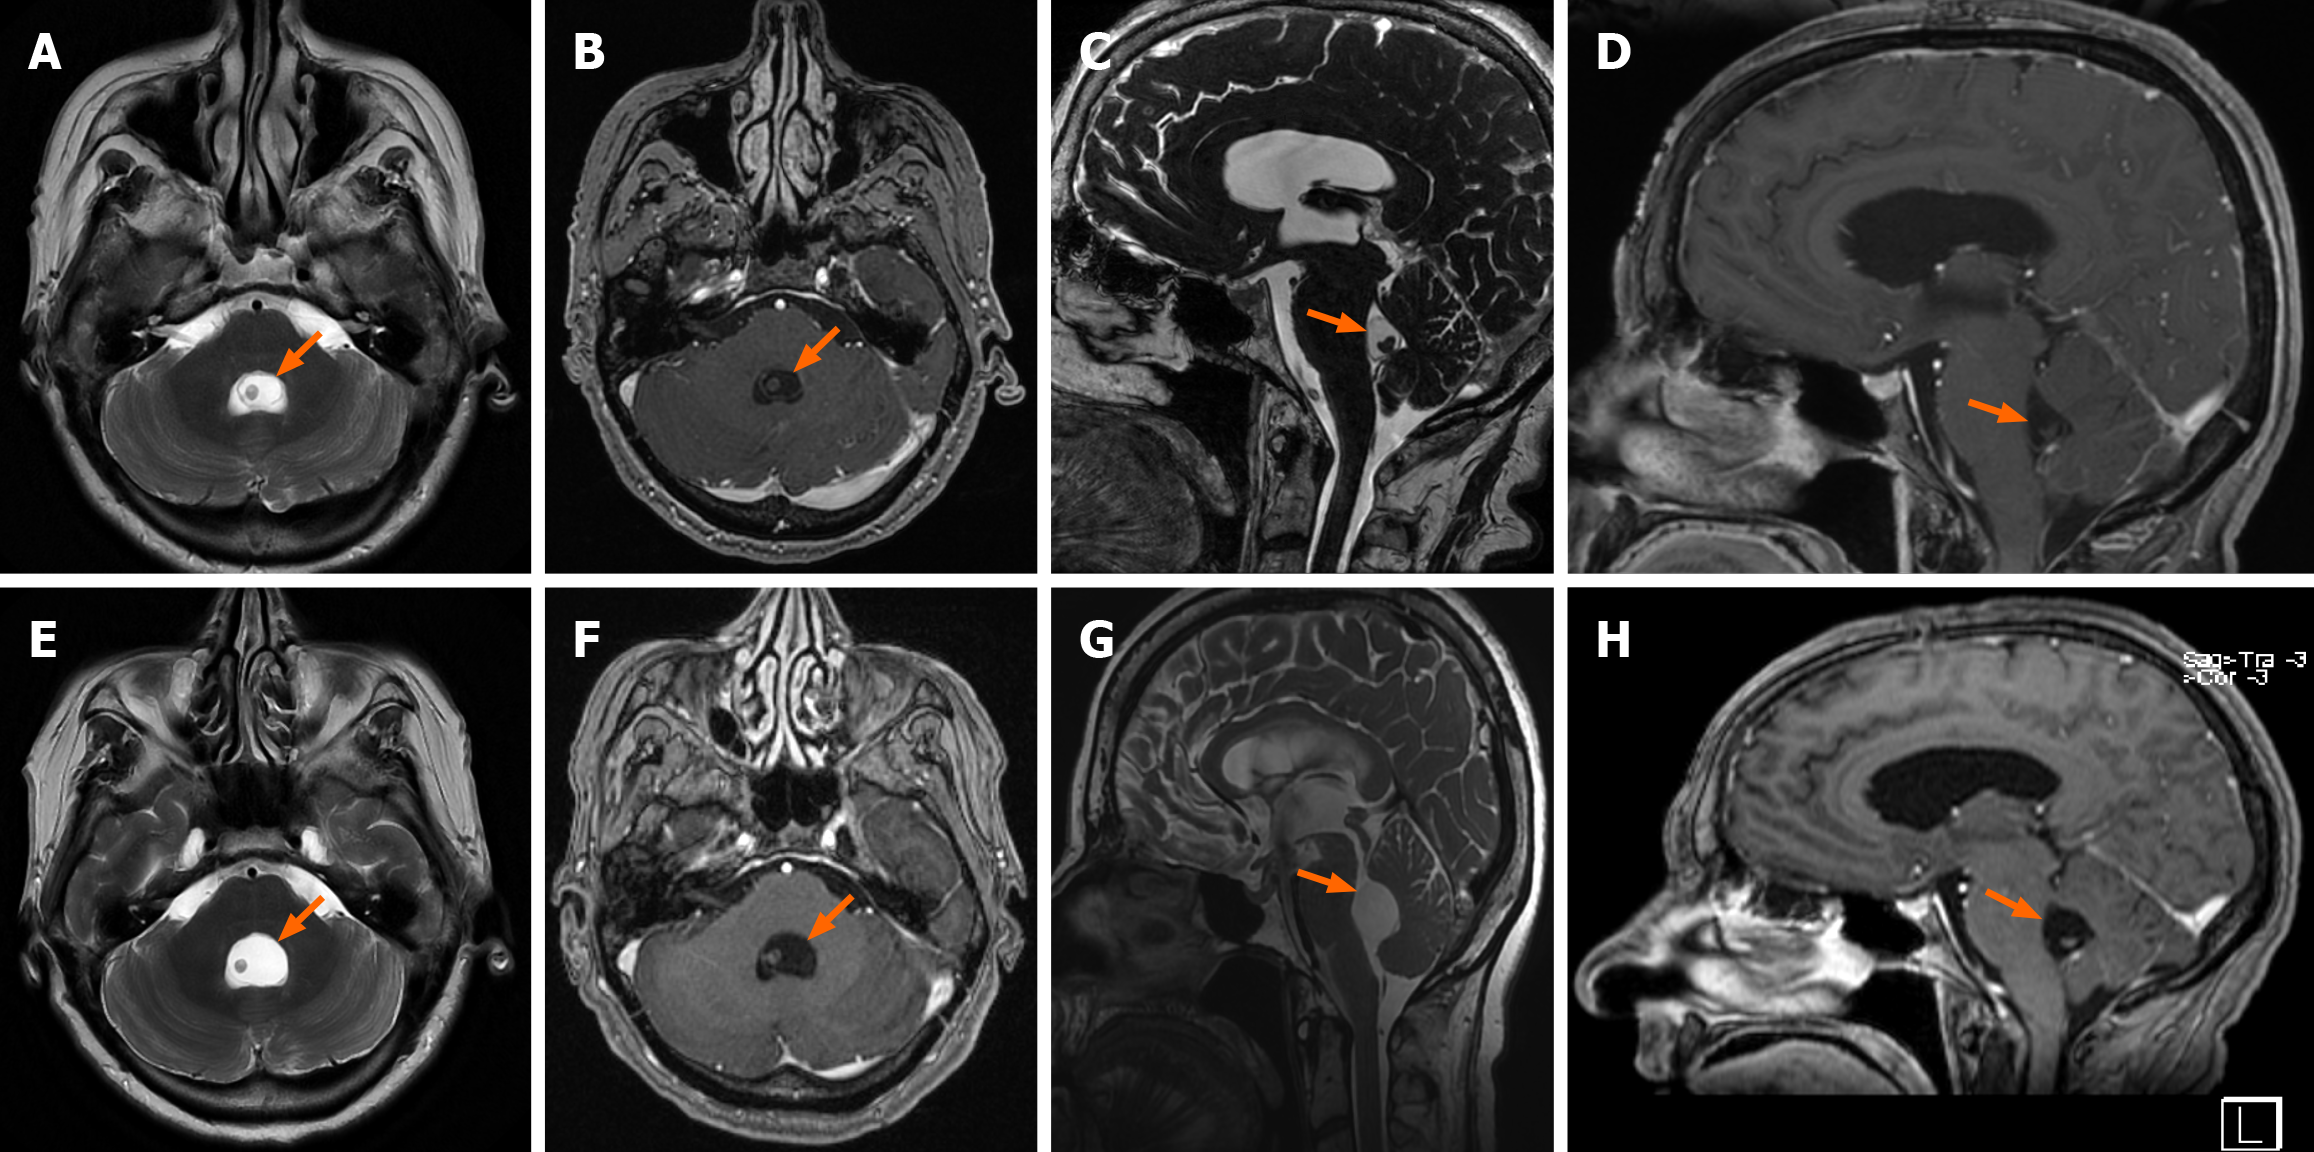

The patient was placed in a prone position and a suboccipital telovelar approach was performed to reach the fourth ventricle. The cyst was identified and microsurgically dissected from the ependyma, allowing en bloc removal without any rupture (Figure 2). Cerebrospinal fluid (CSF) flow was successfully restored. Perioperative corticosteroid therapy was administered to reduce the inflammatory response.

Postoperative MRI showed a gross total removal of the ventricular NCC and a marked reduction in ventricular size (Figure 3). Histopathological analysis confirmed the lesion as a Taenia solium cyst in the vesicular stage. After consultation with infectious disease specialists, antiparasitic therapy was withheld due to the lack of evidence supporting its benefit for solitary intraventricular cysts.